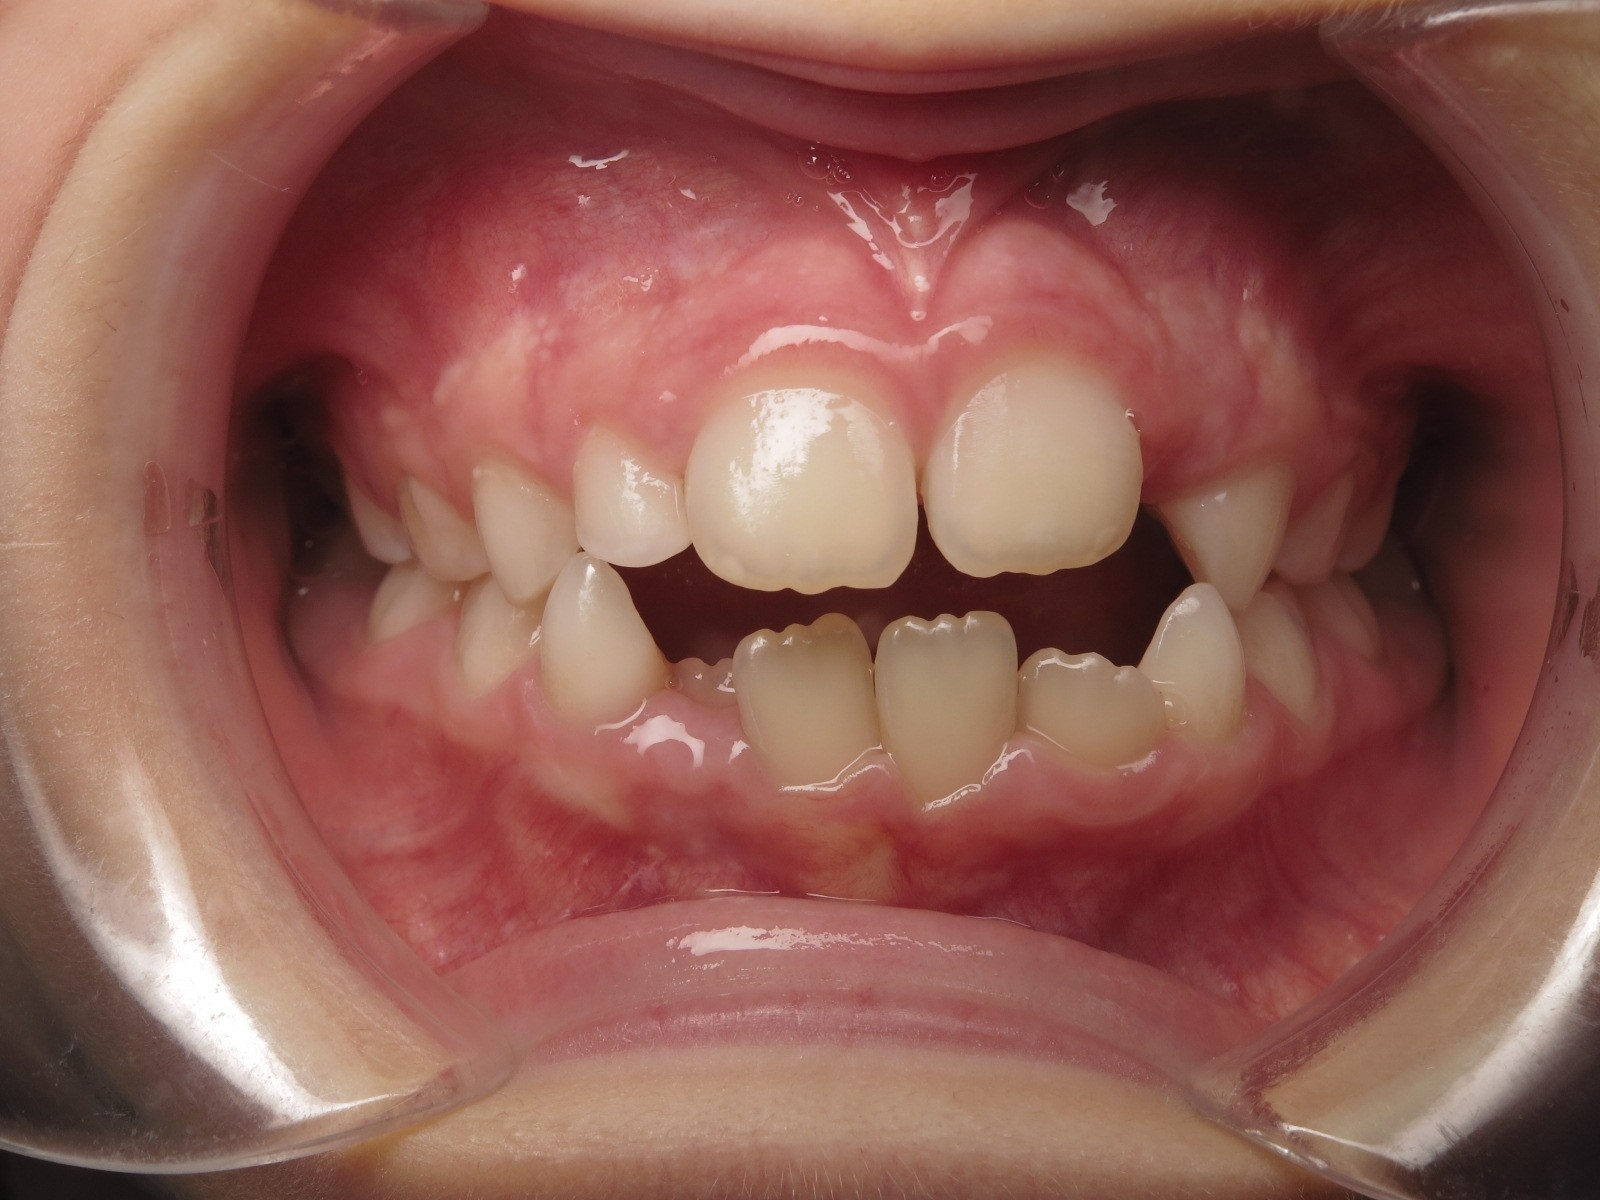

14 béance inversé gauche 5 ans

inversion postérieur coté droit et espace entre l'arcade du haut et du bas (béance)

surveillance évolution de la dentition pendant 27 mois

appareillage mobile pendant 14 mois